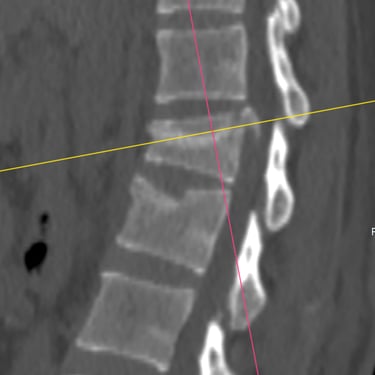

Fractura Vertebral Lumbar: Estabilización Segura con Fijación Transpedicular (FTP)

La fractura vertebral lumbar es una lesión que puede comprometer la estabilidad de la columna y las estructuras neurológicas. En casos seleccionados, el tratamiento quirúrgico mediante artrodesis con fijación transpedicular (FTP) ofrece una estabilización sólida de los segmentos afectados, restaurando la alineación vertebral y permitiendo una movilización temprana. Esta técnica reduce el dolor, previene deformidades progresivas y protege las raíces nerviosas. La intervención oportuna, acompañada de una adecuada rehabilitación, contribuye a una recuperación funcional segura y a una mejora significativa en la calidad de vida del paciente.